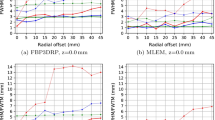

Point source resolution following OSEM 3-D reconstruction was 4.17 mm (FWHM) at 0 cm (centre FOV) and deteriorated to 5.37 mm at a 15-cm radial offset. Spatial resolution was better with PSF reconstruction: 2.09 mm and =3 mm at 0- and 15-cm radial offset, respectively (Fig. 1a).

FWHM of the PSF of point sources imaged in air following OSEM 3-D algorithm and PSF reconstruction (a). SOR, defined as the activity ratio in air- and water-filled cylinders (10 mm in diameter) versus surrounding activity (b). RCs defined as the ratio of measured and true activity concentration as a function of sphere diameters following OSEM 3-D and PSF reconstruction (c, d). Phantom data are given for phantoms placed either at the centre of the FOV or at a 5-cm radial offset and imaged without or with additional cylindrical sources mimicking multiple rodents

For a centrally positioned phantom, the RC for the three largest spheres were lower for images reconstructed with the OSEM 3-D algorithm than for those following PSF reconstruction. For the two smallest spheres the RC decreased significantly for both reconstruction methods although the PSF reconstruction still leads to slightly higher RC values (Fig. 1c, d).

Still, the RCs for the 7.86-mm sphere, which represents a common lesion size in mice bearing subcutaneous tumours [23, 24], were 0.42 for OSEM reconstruction and 0.76 for PSF reconstruction when the phantom was imaged in an off-centred position together with two additional sources. For this lesion, the percentage of variation between RC values for an off-centred acquisition, compared to centred acquisition, was −2.3% in the presence of additional scatter and attenuation sources and −1.1% in the case of a single phantom imaged in the central FOV.

SORs for the water-filled and air-filled cylinders were 4.4 and 6%, respectively. When imaging two additional sources to mimic scatter events introduced when imaging three mice simultaneously, SORs increased to 5.3% in water and 7.5% in air. In contrast, when images were reconstructed with OSEM 3-D SORs were greater than 13% (Fig. 1b).

Phantom studies (Fig. 1) showed good RC values for a 7.86-mm sphere, which represents a common lesion size in mice bearing subcutaneous tumours [23, 24]. RC degrades for very small lesions with only a minor benefit for PSF reconstruction as shown in Fig. 1. Also, SORs were altered by the presence of additional scatter sources in the FOV. Taken together, these results suggest that clinical PET/CT with PSF reconstruction should be restricted to mice model with tumours >7 mm and that other studies like 18F-FDG brain studies of small structures may not provide accurate quantitative data, because of a significant partial volume effect and spillover effect from areas with intense uptake, such as the harderian glands.